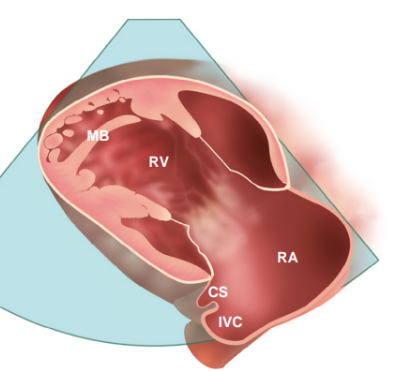

Draw and label the RVIT in parasternal window.